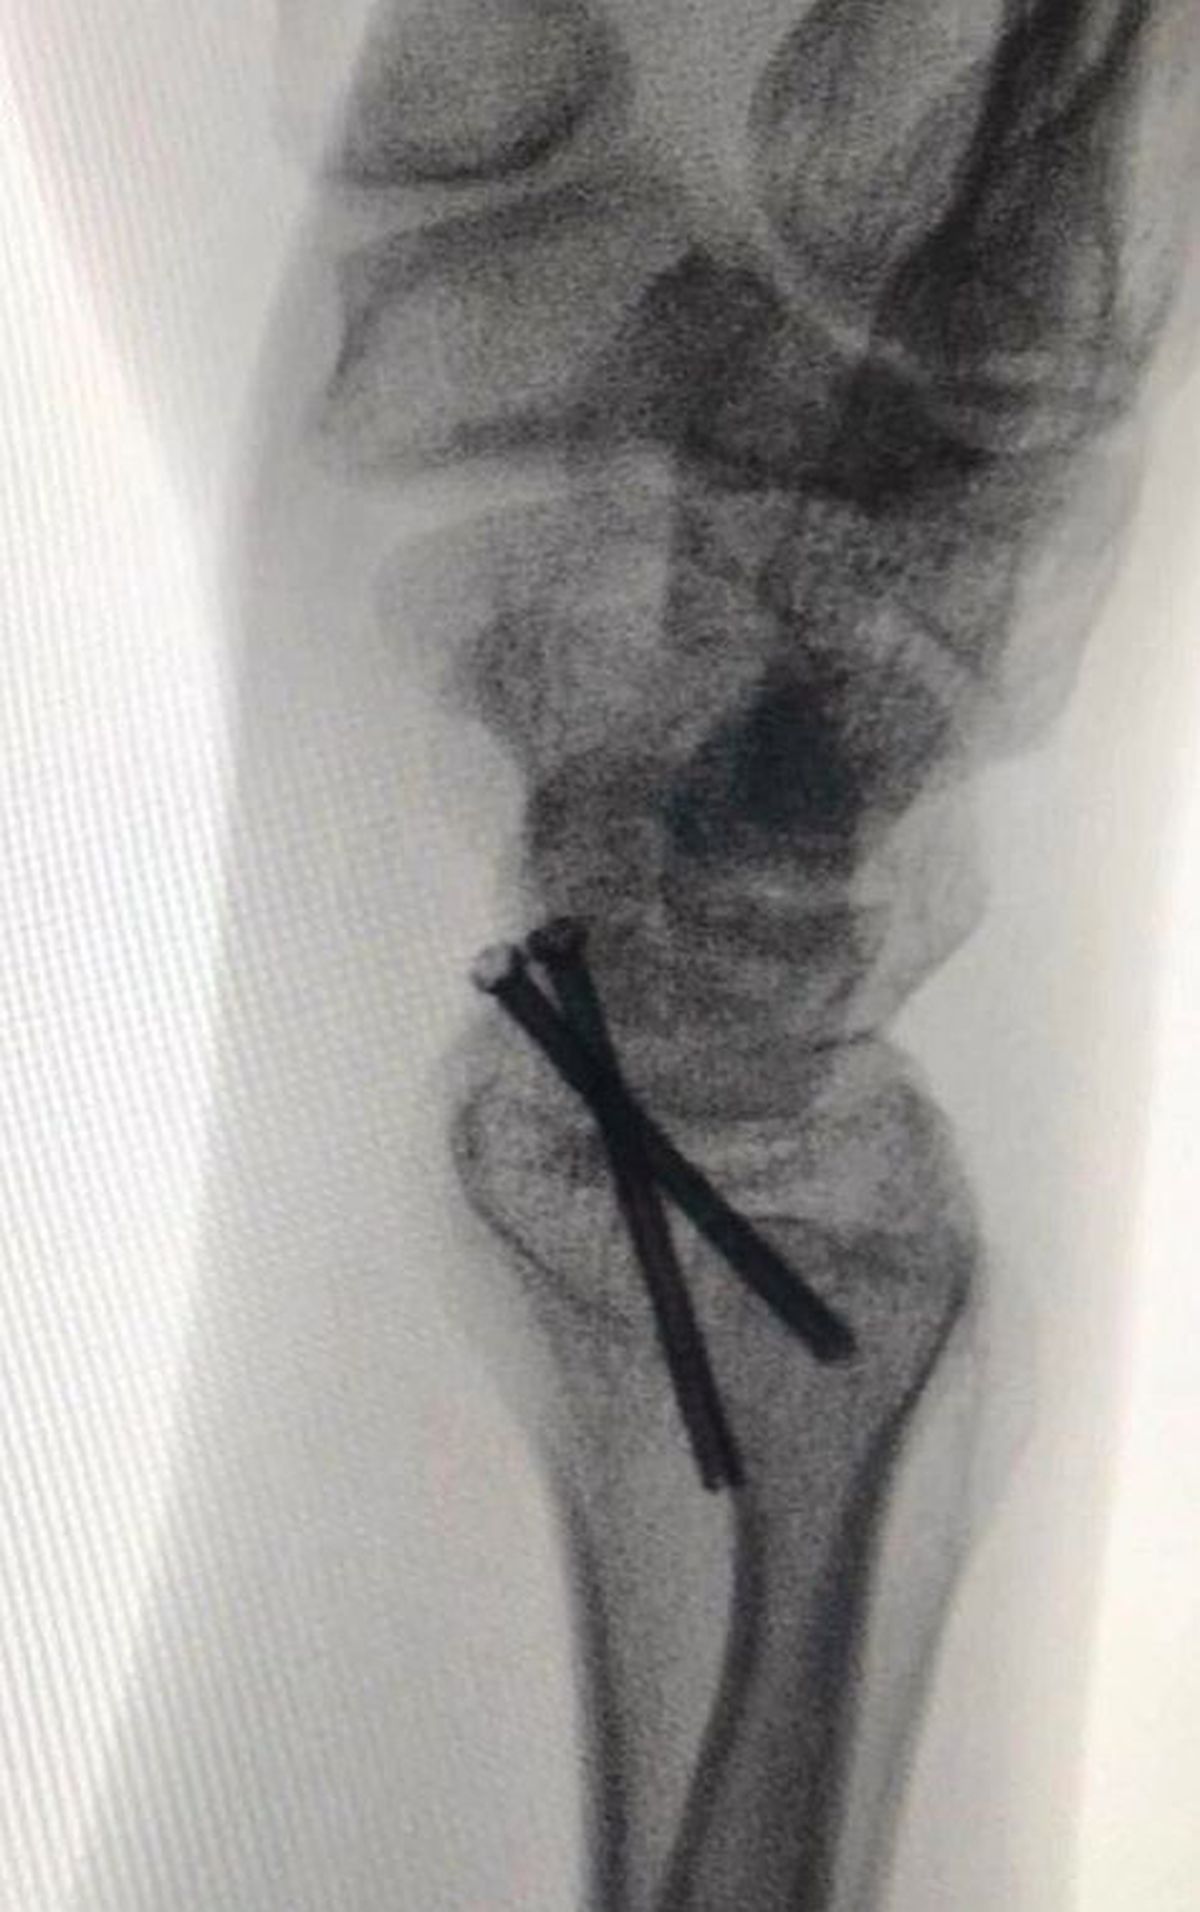

Foto 7/34